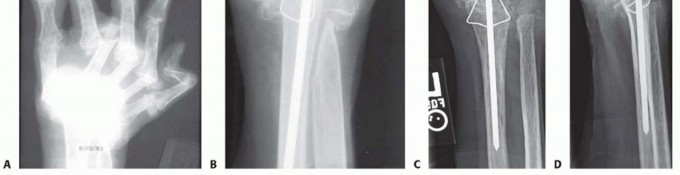

Plate and Screw Osteosynthesis

With the joints meticulously prepared, the focus shifts to rigid internal fixation. The pre-contoured dorsal wrist fusion plate is introduced into the surgical field. The plate is positioned such that its proximal segment lies flat against the flat dorsal surface of the distal radius, while its distal segment rests securely on the dorsal cortex of the third metacarpal. Intraoperative fluoroscopy is utilized extensively at this stage to confirm optimal plate positioning in both the coronal and sagittal planes. The surgeon must ensure that the pre-contoured bend of the plate aligns perfectly with the radiocarpal joint, imparting the desired 20 to 30 degrees of extension and approximately 5 to 10 degrees of ulnar deviation, which optimizes the biomechanical axis of the hand.

Image

Fixation typically begins distally. A non-locking cortical screw is placed through the oblong hole in the distal segment of the plate into the diaphysis of the third metacarpal. This allows for minor proximal-distal adjustments. Once the distal position is confirmed, a corresponding non-locking screw is placed in the proximal oblong hole on the radial shaft. With the plate provisionally secured, the surgeon applies axial compression across the carpus. This can be achieved manually or by using an articulated tensioning device. The remaining screw holes are then systematically filled. Modern plate designs incorporate specialized locking holes over the carpal segment, allowing for the insertion of locking screws into the capitate and occasionally the lunate or scaphoid. This creates a highly stable, fixed-angle construct that is highly resistant to pullout, even in osteopenic bone.